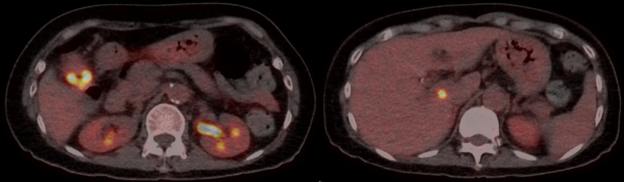

A 70-year-old woman with CREST syndrome on long-term mycophenolate underwent [¹⁸F]-FDG PET/CT for evaluation of a growing right lung nodule detected on high-resolution CT.